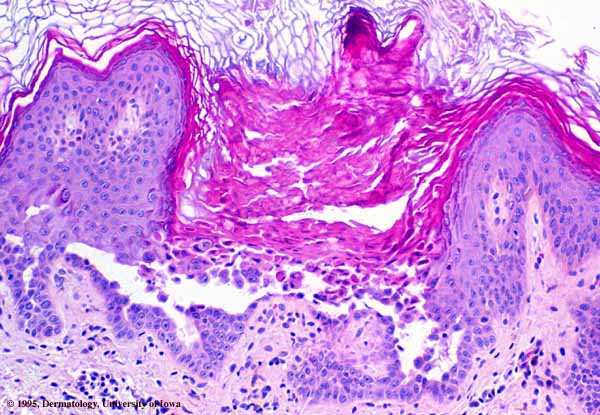

The characteristic changes in Darier’s disease include the following: (a) a peculiar form of dyskeratosis resulting in the formation of corps ronds and grains; (b) suprabasal acantholysis leading to the formation of suprabasal clefts or lacunae; and (c) irregular upward proliferation into the lacunae of papillae lined with a single layer of basal cells, so-called villi (Fig. 6-27). There are also papillomatosis, acanthosis, and hyperkeratosis. The dermis shows a chronic inflammatory infiltrate. In some cases, there is downward proliferation of epidermal cells into the dermis.

The corps ronds occur in the upper stratum malpighii, particularly in the granular and horny layers; grains are found in the horny layer and as acantholytic cells within the lacunae. Corps ronds possess a central homogeneous, basophilic,

pyknotic nucleus that is surrounded by a clear halo. By virtue of size and the conspicuous halo, corps ronds stand out clearly . Peripheral to the halo lies basophilic dyskeratotic material as a shell . The nonstaining halo in some instances is partially replaced by homogeneous, eosinophilic dyskeratotic material . Compared with the corps ronds, the grains are much less conspicuous. They resemble parakeratotic cells but are somewhat larger. The nuclei of grains are elongated and often grain shaped and are surrounded by homogeneous dyskeratotic material that usually stains basophilic but may stain eosinophilic. The lacunae represent small, slitlike intraepidermal vesicles most commonly located directly above the basal layer. They contain acantholytic cells and show premature partial keratinization. Because of shrinkage, some of them are elongated, and these then appear identical with the grains in the horny layer. The villi projecting into the lacunae may be quite tortuous, so on histologic examination, some of them appear in cross section as rounded dermal structures lined by a solitary row of basal cells .